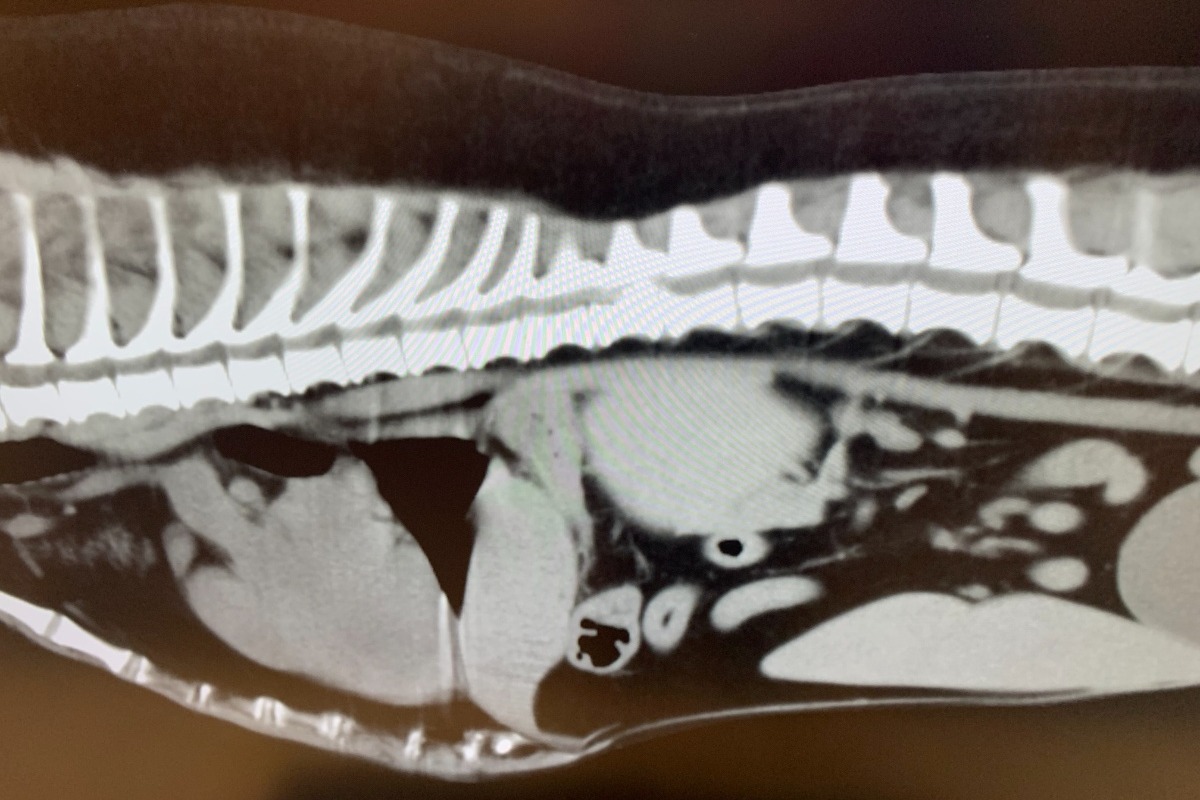

Last week, I started to notice Win had a loss of mobility. I took her to our vet and she was treated for back pain and given some anti-inflammatory medication. The next day when I got home from work, she could barely walk and had lost control of her back legs.. a heartbreaking scene to witness. We went to the Flagstaff vet hospital where she received a CT scan and I was informed that she has a severe slipped disc that was cutting off 75% of her spinal cord. She needed immediate surgery. The surgery is taking place as I write this.